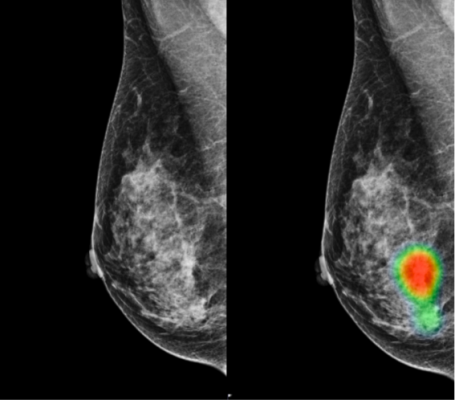

CASE STUDIES

Real-Life Success Stories and Medical Breakthroughs

🩺 Case Report: Laparoscopic Ovarian Cystectomy...

INTRODUCTION: ECTOPIC PREGNANCY OCCURS WHEN A F...